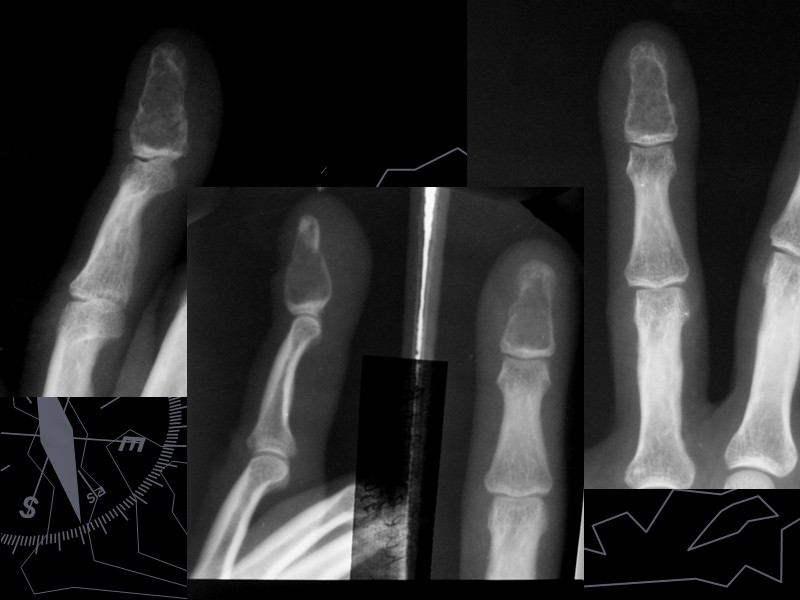

Хондрома До 10-15% от всех доброкачественных костных опухолей Выявляется чаще в возрасте от 10 до 40 лет Чаще множественные поражения (двусторонние, не симметричные) Малигнизируется в хондросаркому (чаще при локализации в ребрах, длинных трубчатых костях, костях таза) Поражаются преимущественно короткие трубчатые кости (фаланги), ребра, грудина, Редко - позвонки, кости таза, длинные трубчатые кости Солитарные поражения длинных трубчатых костей – дифференцируем с кистой, фибромой, метастазом

По расположению в кости выделяют: Экхондрома (переферически) Проявляется либо краевой деструкцией, на уровне которой располагается добавочное образование с широким диапазоном всевозможных обызвествлений. Энхондрома (центрально) Выглядит как очаг вздутия, негомогенной структуры (хрящевой фон с вкраплениями костного вещества), окруженный замыкательной пластинкой – «скорлупой» За счет вздутия и истончения кортикального слоя часто осложняется патологическим переломом